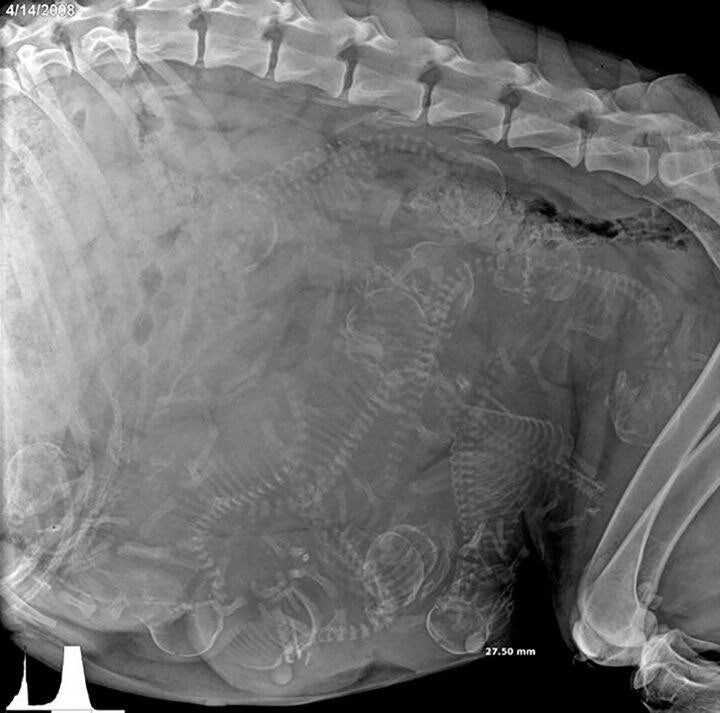

임신한 강아지 엑스레이 촬영 작성자 정보 백억랜드 쪽지보내기 메일보내기 자기소개 아이디로 검색 전체게시물 쪽지보내기 메일보내기 자기소개 아이디로 검색 전체게시물 작성 작성일 2025.05.10 19:16 컨텐츠 정보 850 조회 10 추천 목록 본문 10 추천 관련자료 이전 92세 할아버지의 인생의 조언.jpg 작성일 2025.05.10 19:39 다음 해피밀 크록스 작성일 2025.05.10 18:57 댓글 0 등록된 댓글이 없습니다. 로그인한 회원만 댓글 등록이 가능합니다. 목록